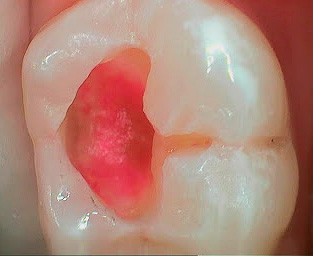

Degli ingredienti attivi nei marcatori di carie, la fucsina acida è il più comunemente usato - un noto colorante sintetico che ha un colore rosso intenso in soluzioni acquose. La foto mostra come le parti cariate del dente sono macchiate con esso: